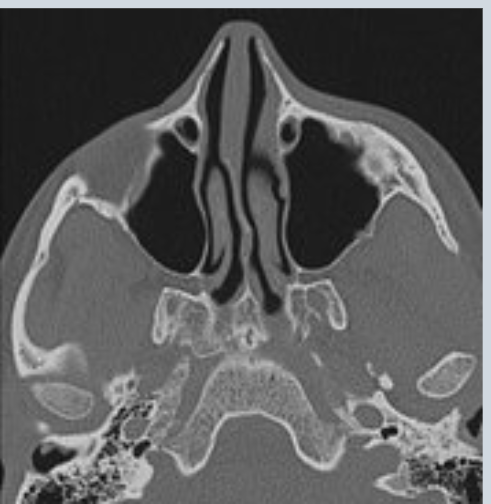

what imaging tests can be done to diagnose nasal cavity/sinus cancers

CT (cortical bone erosion through cribriform plate)

MR (direct intracranial/leptomeningeal spread)

PET or bone scan

what would be the diagnosis from this scan

left paranasal sinus invaded with tumor

right maxillary bone has been fractured/destroyed by a tumor